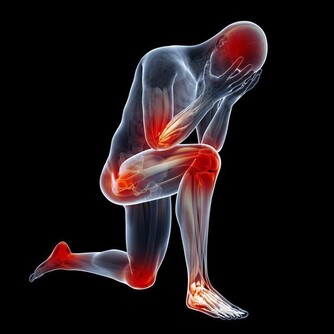

*****3、經常腹瀉*****

如果起床之後總是有拉肚子的表現,需要引起重視。保持健康,消化系統維持功能良好,在正常消化的情況下獲取了食物,裡面的營養物質被人體吸收,代謝廢物可以順利排出,排泄出來的糞便為黃褐色,長條狀,這是健康的體現。

但是,有部分人起床之後就想要上廁所,排泄出來的糞便卻有異樣,無論是氣味,顏色還是狀態改變都要引起重視,膽囊、胰腺、肝臟發生病變同樣也會影響正常的糞便排泄。另外,常見的消化系統疾病發展,患者也會有特殊的排便表現,需要了解原因後對症處理,才能讓腹瀉,消化不良等情況緩解。

由此可見,起床時有不良症狀引起重視,通過檢查可以明確病因,如果對身體有影響,第一時間展開治療,才能在疾病改善之後提高生活質量,延長壽命。